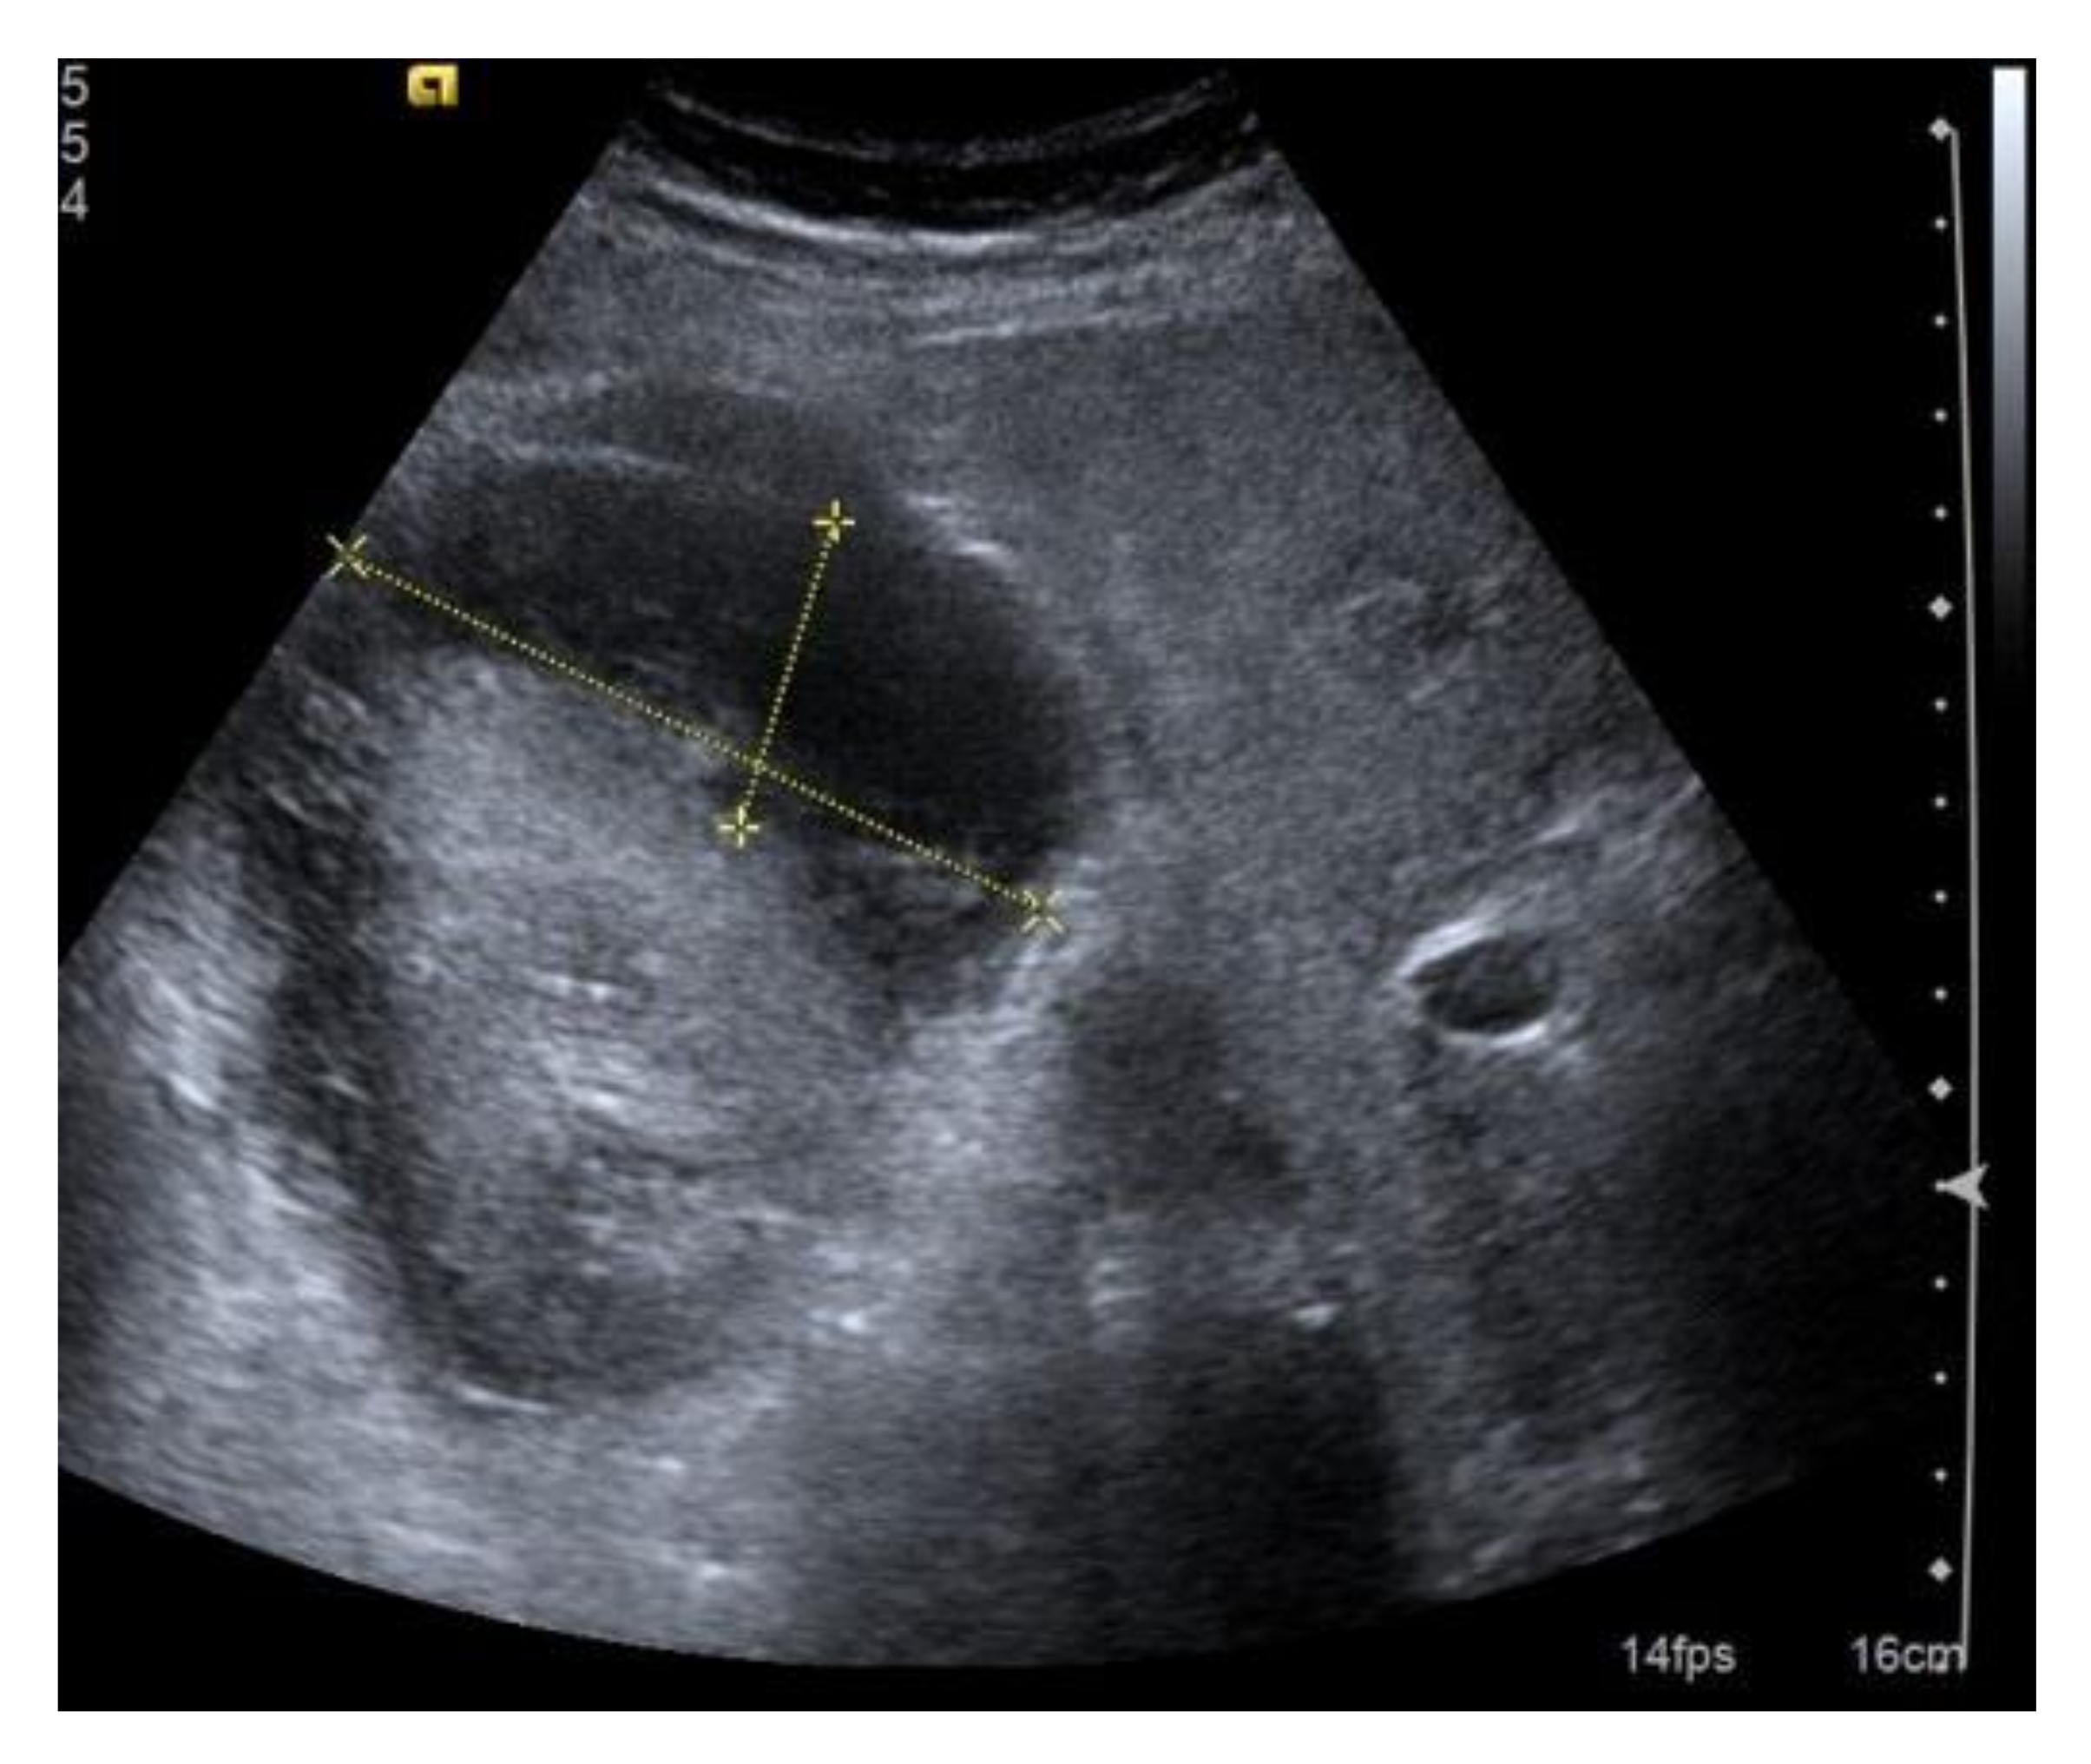

12. Complications

Although the ultrasound-guided execution of PRB after a thorough clinical assessment is relatively safe, adverse events are not infrequent and can be potentially fatal. Bleeding is certainly the most common complication. Hematoma (75% of complications) is generally well-recognizable with post-procedural ultrasound. It can be subcapsular, retroperitoneal or, rarely due to injury of the lumbar vessels (Figure 7). It has been described that the majority of patients with a detectable hematoma on the control ultrasound had minor or major complications (including bleeding requiring transfusion or radiologist intervention) in the few hours following the procedure. Hematoma is, therefore, a predictor of bleeding-related complications, but it seems as if there is no significant relationship between its size and the extent of bleeding [24,25]. Symptoms range from completely silent (small subcapsular hematomas) to hematuria, flank pain, anemia, and shock. The control of blood pressure and local compression may be sufficient in the management of subcapsular bleeding, while in the most severe cases, a super-selective angiography of the arterial vessels involved and subsequent embolization must be used [6]. Surgical treatment (which may include nephrectomy in fewer than 1% of complicated cases) is reserved for cases that cannot be treated intravascularly or cases of hemodynamic instability [7]. A special case of subcapsular bleeding is the page kidney, which is caused by the accumulation of blood in the perinephric or subcapsular space, resulting in extrinsic compression of the involved kidney, renal ischemia, activation of the renin–angiotensin–aldosterone system, and systemic hypertension. Arteriovenous fistula (AVF) is a relatively rare complication of kidney biopsy detectable with ECD, which is especially common in transplanted kidneys (described in up to 10% of biopsies). The treatment can be conservative or interventional in confirmed cases.

Figure 7.

Extensive post-bioptic subcapsular hematoma; the anecogenicity of the effusion indicates that the bleeding is recent, but it is not possible to obtain reliable information as to whether bleeding still exists. Size is an unreliable parameter in these cases. In the presence of post-biopsy hematoma, non-invasive dynamic contrast studies (CEUS or contrast-enhanced CT) can be very useful to evaluate a bleeding source and any rarer post-biopsy vascular complications.